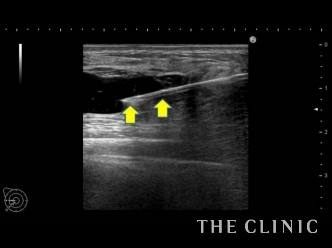

この方は施術を受けたクリニックでヒアルロン酸溶解の処置を受けられているのですが、まだ残っている気がするためエコー検査に来院されました。

実際に診てみると、確かにヒアルロン酸が残っていて、黒い塊として確認できました。

触診では困難なため、リアルタイムで映し出されるエコーの映像を確認しながら、ヒアルロン酸(しこり内)に確実に溶解液(ヒアルロニダーゼ)を注入します。

これにより、ヒアルロン酸の加水分解が始まり数十秒でジェル状に。それを吸引除去しました。

画像の矢印の少し上、真ん中から右端へ入っている白い線が先程の治療で使った吸引管ですが、ヒアルロン酸を除去したことにより、施術直後からしこりがなくなっていることが確認できます。